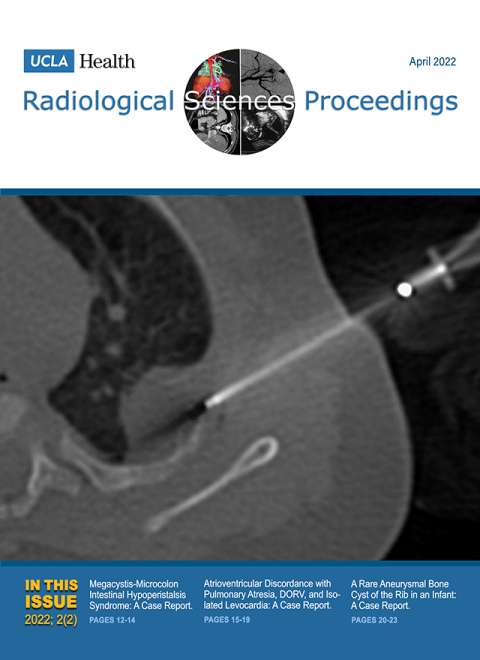

April 2022

Volume 2, Issue 2

- Megacystis-Microcolon–Intestinal Hypoperistalsis Syndrome: A Case Report

- Atrioventricular Discordance with Pulmonary Atresia, Double-outlet Right Ventricle, and Isolated Levocardia: A Case Report of a Rare Congenital Heart Disease

- A Rare Aneurysmal Bone Cyst of the Rib in an Infant: A Case Report